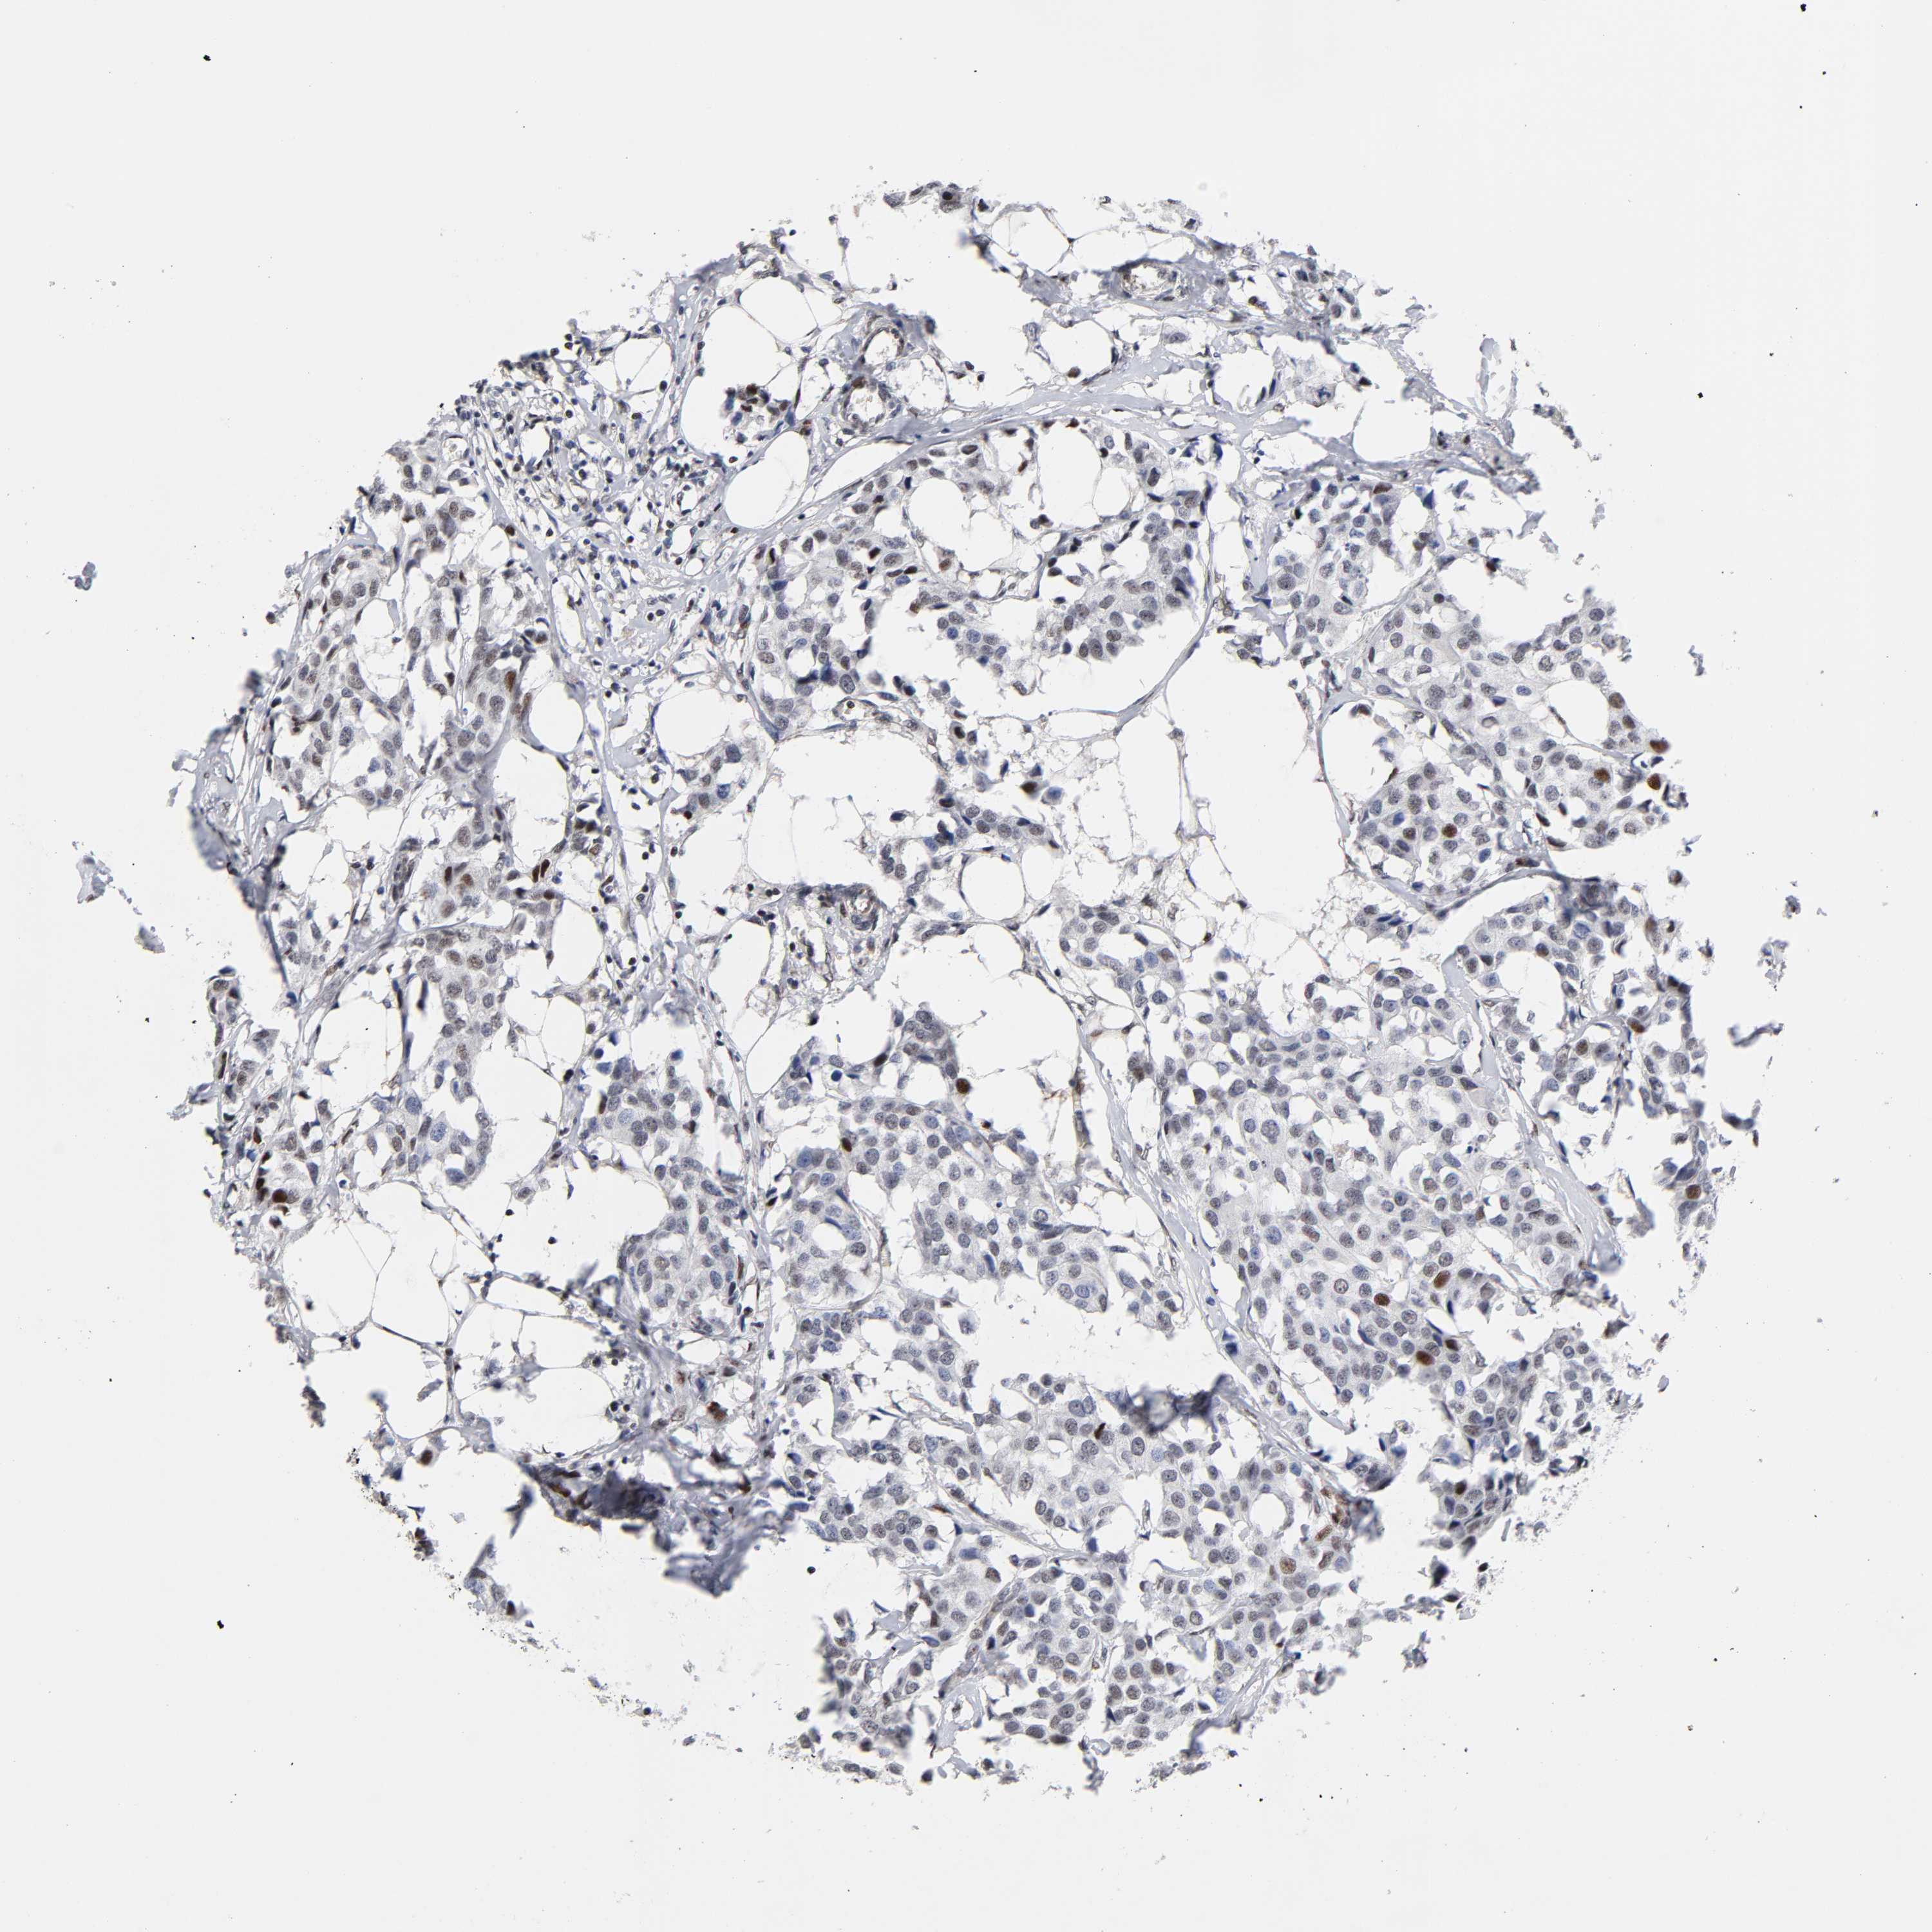

BRCA TCGA BRCA VALIDATION PROTEIN EXPRESSION

ANTIBODIES

AND

VALIDATION